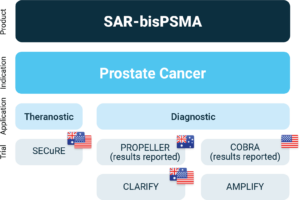

Clarity Pharmaceuticals a clinical stage radiopharmaceutical company with a mission to develop next-generation products that improve treatment outcomes for children and adults with cancer, is pleased to announce it will be commencing a pivotal Phase III trial of its 64Cu-SAR-bisPSMA diagnostic in patients with BCR of prostate cancer following a successful end of phase meeting with the U.S. FDA. The trial, named AMPLIFY (64Cu-SAR-bisPSMA Positron Emission Tomography: A Phase 3 Study of Participants with Biochemical Recurrence of Prostate Cancer), is expected to begin patient recruitment in early 2025.

The AMPLIFY trial will be a non-randomised, single-arm, open-label, multi-centre, Phase III diagnostic clinical trial of 64Cu-SAR-bisPSMA Positron Emission Tomography (PET) in approximately 220 participants with rising or detectable PSA after initial definitive treatment. As a pivotal trial, the final study results are intended to provide sufficient evidence to support an application to the FDA for approval of 64Cu-SAR-bisPSMA as a new diagnostic imaging agent in prostate cancer.

The initiation of the AMPLIFY trial is supported by compelling preclinical and clinical trial data to date, including the Phase I/II COBRA trial in patients with BCR of prostate cancer, and the Phase I PROPELLER trial in patients with confirmed prostate cancer pre-prostatectomy/pre-definitive treatment, which have been accepted for presentation or presented at leading medical conferences, including the Society of Nuclear Medicine and Molecular Imaging (SNMMI) Annual Meeting, European Association of Nuclear Medicine (EANM) Congress, American Society of Clinical Oncology (ASCO) Annual Meeting, ASCO Genitourinary Cancers Symposium and others. The data showed that 64Cu-SAR-bisPSMA is safe, and its uptake in prostate-specific membrane antigen (PSMA)-expressing cancer lesions was significantly higher compared to the approved SOC PSMA imaging agents for prostate cancer in Australia and the US. Additionally, data from the COBRA trial established that 64Cu-SAR-bisPSMA was able to detect much smaller lesions than anticipated, including a lesion with a diameter of less than 2 mm, which compares favourably against the SOC PSMA imaging agents. 64Cu-SAR-bisPSMA was also able to identify lesions months prior to these being detected by approved SOC PSMA agents (Figure 1).

Overview of Clarity’s SAR-bisPSMA clinical program